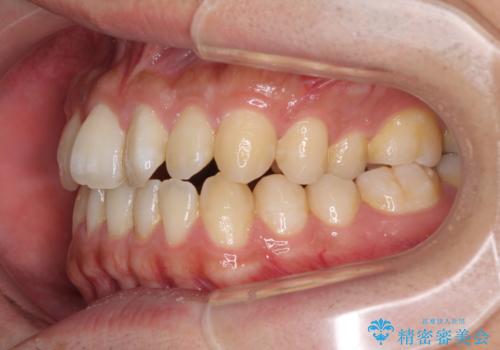

下顎前歯と上顎の部分矯正

- 上下の前歯の叢生を気にして来院された患者様です。

前歯のみの矯正治療を希望でしたが、上顎臼歯が舌側転位していたため、上顎は全体を、下顎は前歯のみを矯正治療することとしました。

矯正治療は上下全顎を行うことが大前提ですが、費用などの点から、今回は部分矯正を選択することとなりました。

患者様本人は咬みにくさを感じていないようですが、部分矯正は咬み合わせの改善が困難であることが多く、咬みにくさが残ることがあります。